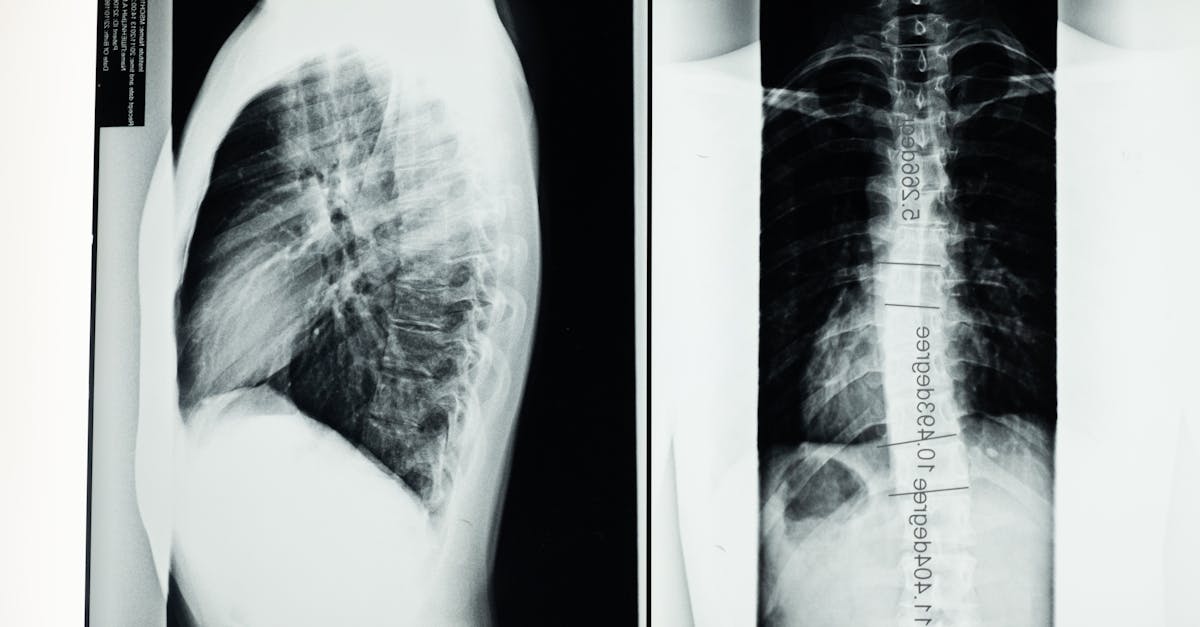

La décompression neurovertébrale est une approche thérapeutique qui utilise une traction douce pour créer de l’espace entre les vertèbres. Cette extra traction réduit la pression exercée sur les nerfs et les disques intervertébraux. En conséquence, elle améliore la circulation sanguine et la nutrition des tissus, ce qui peut réduire la douleur et favoriser la guérison.

Un des principaux avantages de la décompression neurovertébrale réside dans sa capacité à réduire la pression sur les disques intervertébraux. Cette technique utilise un système de traction contrôlée pour créer un espace entre les vertèbres, favorisant ainsi une meilleure circulation des fluides et la réhydratation des disques. Cela est particulièrement bénéfique pour les personnes souffrant de hernies discales, de discopathies dégénératives, ou de douleurs associées à des blessures sportives. En diminuant la douleur, les patients peuvent rapidement retrouver leur niveau d’activité physique.

Tout d’abord, la décompression neurovertébrale facilite la guérison des disques intervertébraux en permettant une traction contrôlée de la colonne vertébrale. Cette méthode réduit significativement la pression exercée sur les nerfs et les muscles, favorisant ainsi une meilleure récupération. Les patients actifs, souvent exposés à des charges physiques importantes, bénéficient particulièrement de cette approche douce, qui évite des traitements plus invasifs, tels que la chirurgie.

Elle utilise une traction douce et contrôlée pour créer une pression négative dans les disques, permettant leur réhydratation et leur repositionnement.